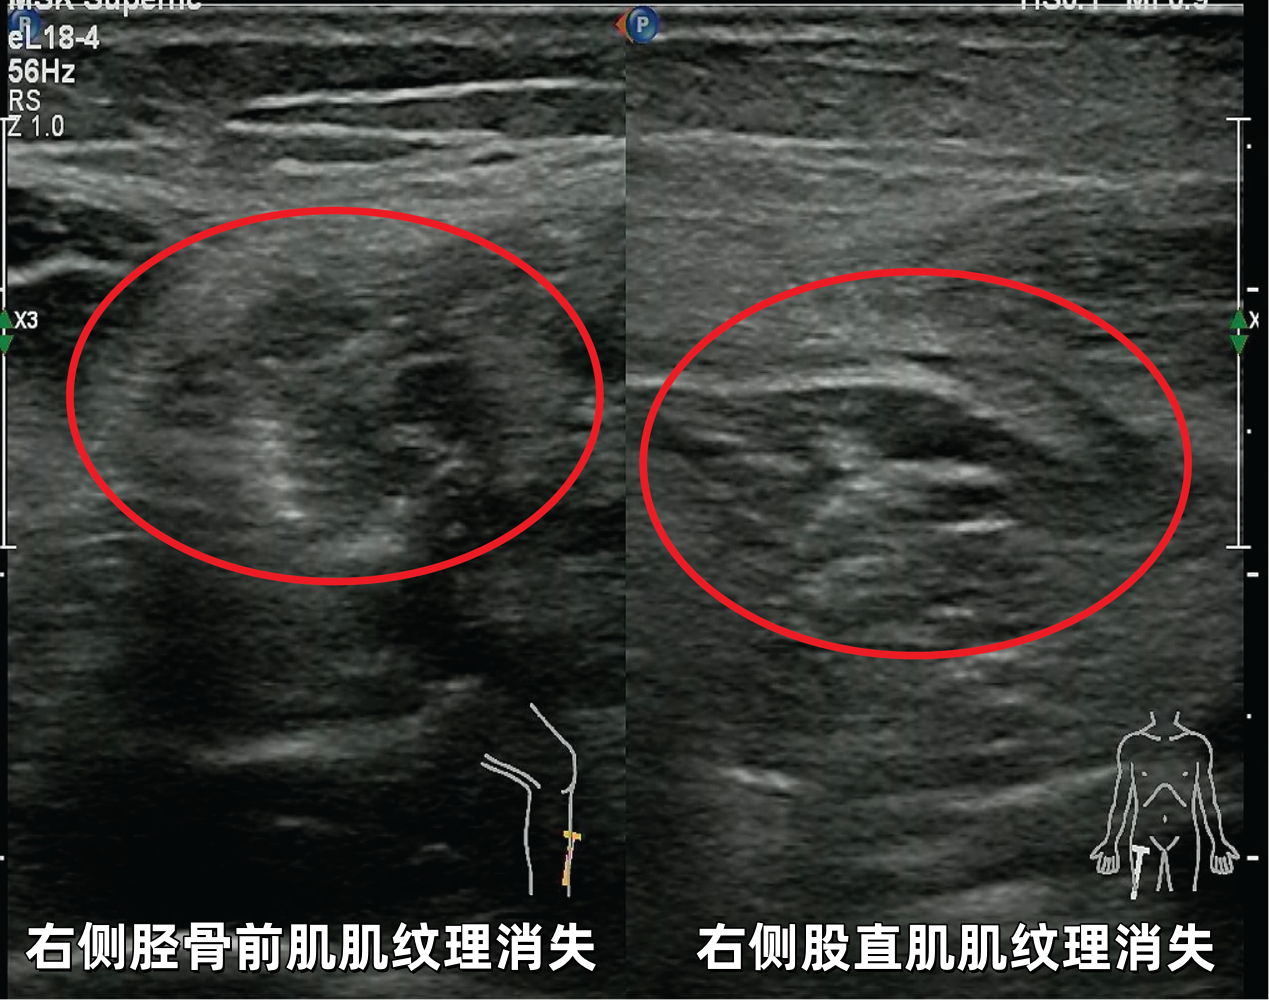

超声影像

当超声探头滑过小轩疼痛无力的四肢时,屏幕上的图像揭示了关键线索:其双臂及大腿的肌肉呈现出特征性的纹理紊乱、结构模糊。

这一清晰直观的影像证据,为临床诊断提供了坚实依据,高度提示为皮肌炎。

部分病例展示